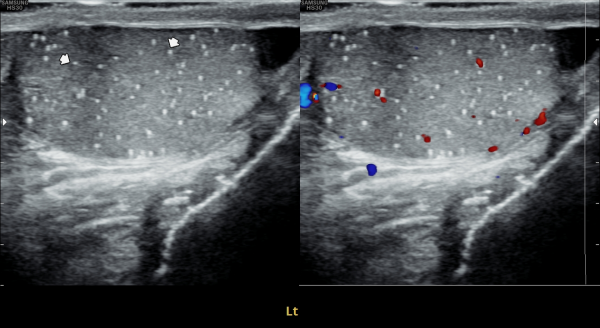

첫 내원 당일 검사한 고환의 초음파 사진상 앉아서 생활하는 직업상 고환 동맥의 순환 장애로 죽상동맥경화증의 소견을 보여 식이요법과 운동요법을 말씀드리고 정관의 표적 치료를 시작한 사진입니다.

On the day of your first visit, the testicular ultrasound showed signs of reduced blood flow in the testicular artery, likely from long hours of sitting. This may have caused early signs of atherosclerosis. We discussed healthy lifestyle changes, including diet and exercise, and started targeted treatment for the vas deferens.

4개월 동안 정관의 표적 치료와 직장 생활중 장시간 앉은 업무를 개선하여 운동을 겸한후 추적 고환의 초음파 사진장

고환동맥의 축상경화증 소견이 치료되고 있는 사진입니다.

This follow-up scrotal ultrasound image, taken after four months of targeted treatment for the vas deferens and lifestyle improvements including reduced prolonged sitting during office work and regular exercise, shows improvement in axial arteriosclerosis of the testicular artery.